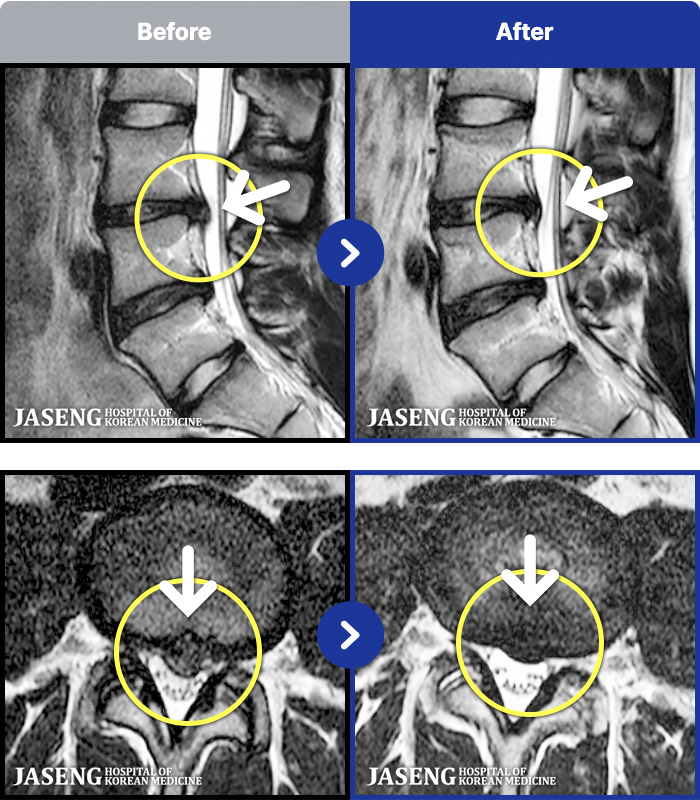

MRI ġ

1,304 MRI ũ ʸ Ȯϼ.